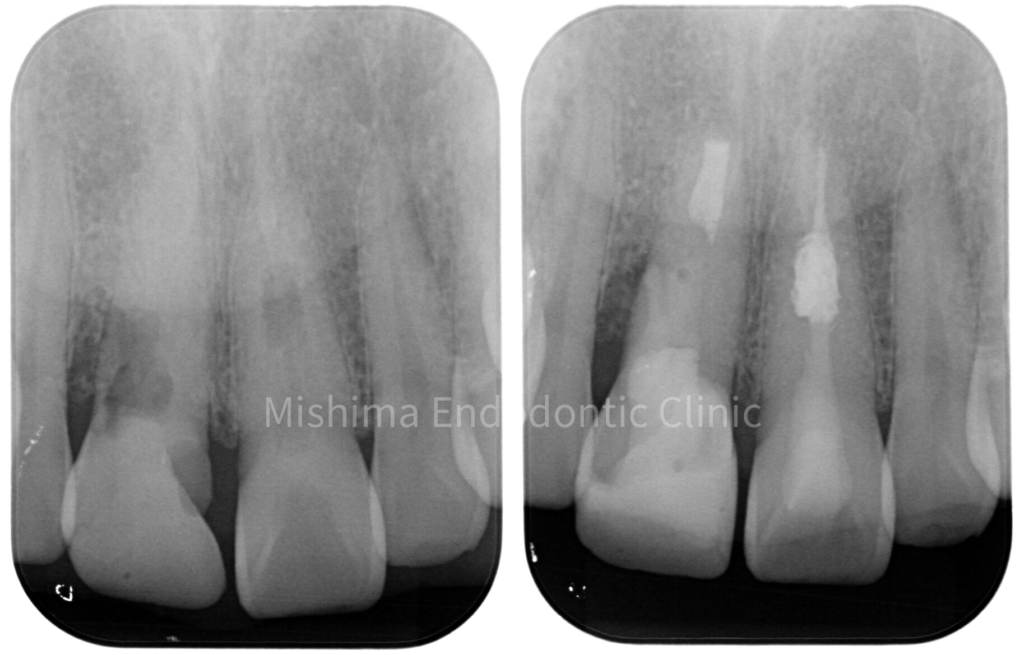

Before

After

| 治療内容 | 6年前にサバイバルゲームでBB弾が歯に当たり、歯が欠けた。 歯髄診査では、11,21ともにEPT+、Cold+。11は侵襲性歯頚部吸収、21は内部の炎症性吸収と診断。また、11にはパーフォレーションも認めた。 21は根管治療、ダイレクトボンディングにて対応。 11は、歯冠部の審美に対してはダイレクトボンディングにて対応。 まず侵襲性歯頚部吸収による吸収部を粘膜剥離しバイオデンティンにて外部より封鎖。後日、パーフォレーション部をバイオデンティンにて根管内部よりリペア。歯髄は正常と診断したが、予防的に根管治療を行うこととした。歯冠部からのアクセスが困難だったため、逆根管治療(歯根端切除術)にて対応。 |